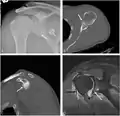

CT scan showing a bony Bankart lesion at the antero-inferior glenoid